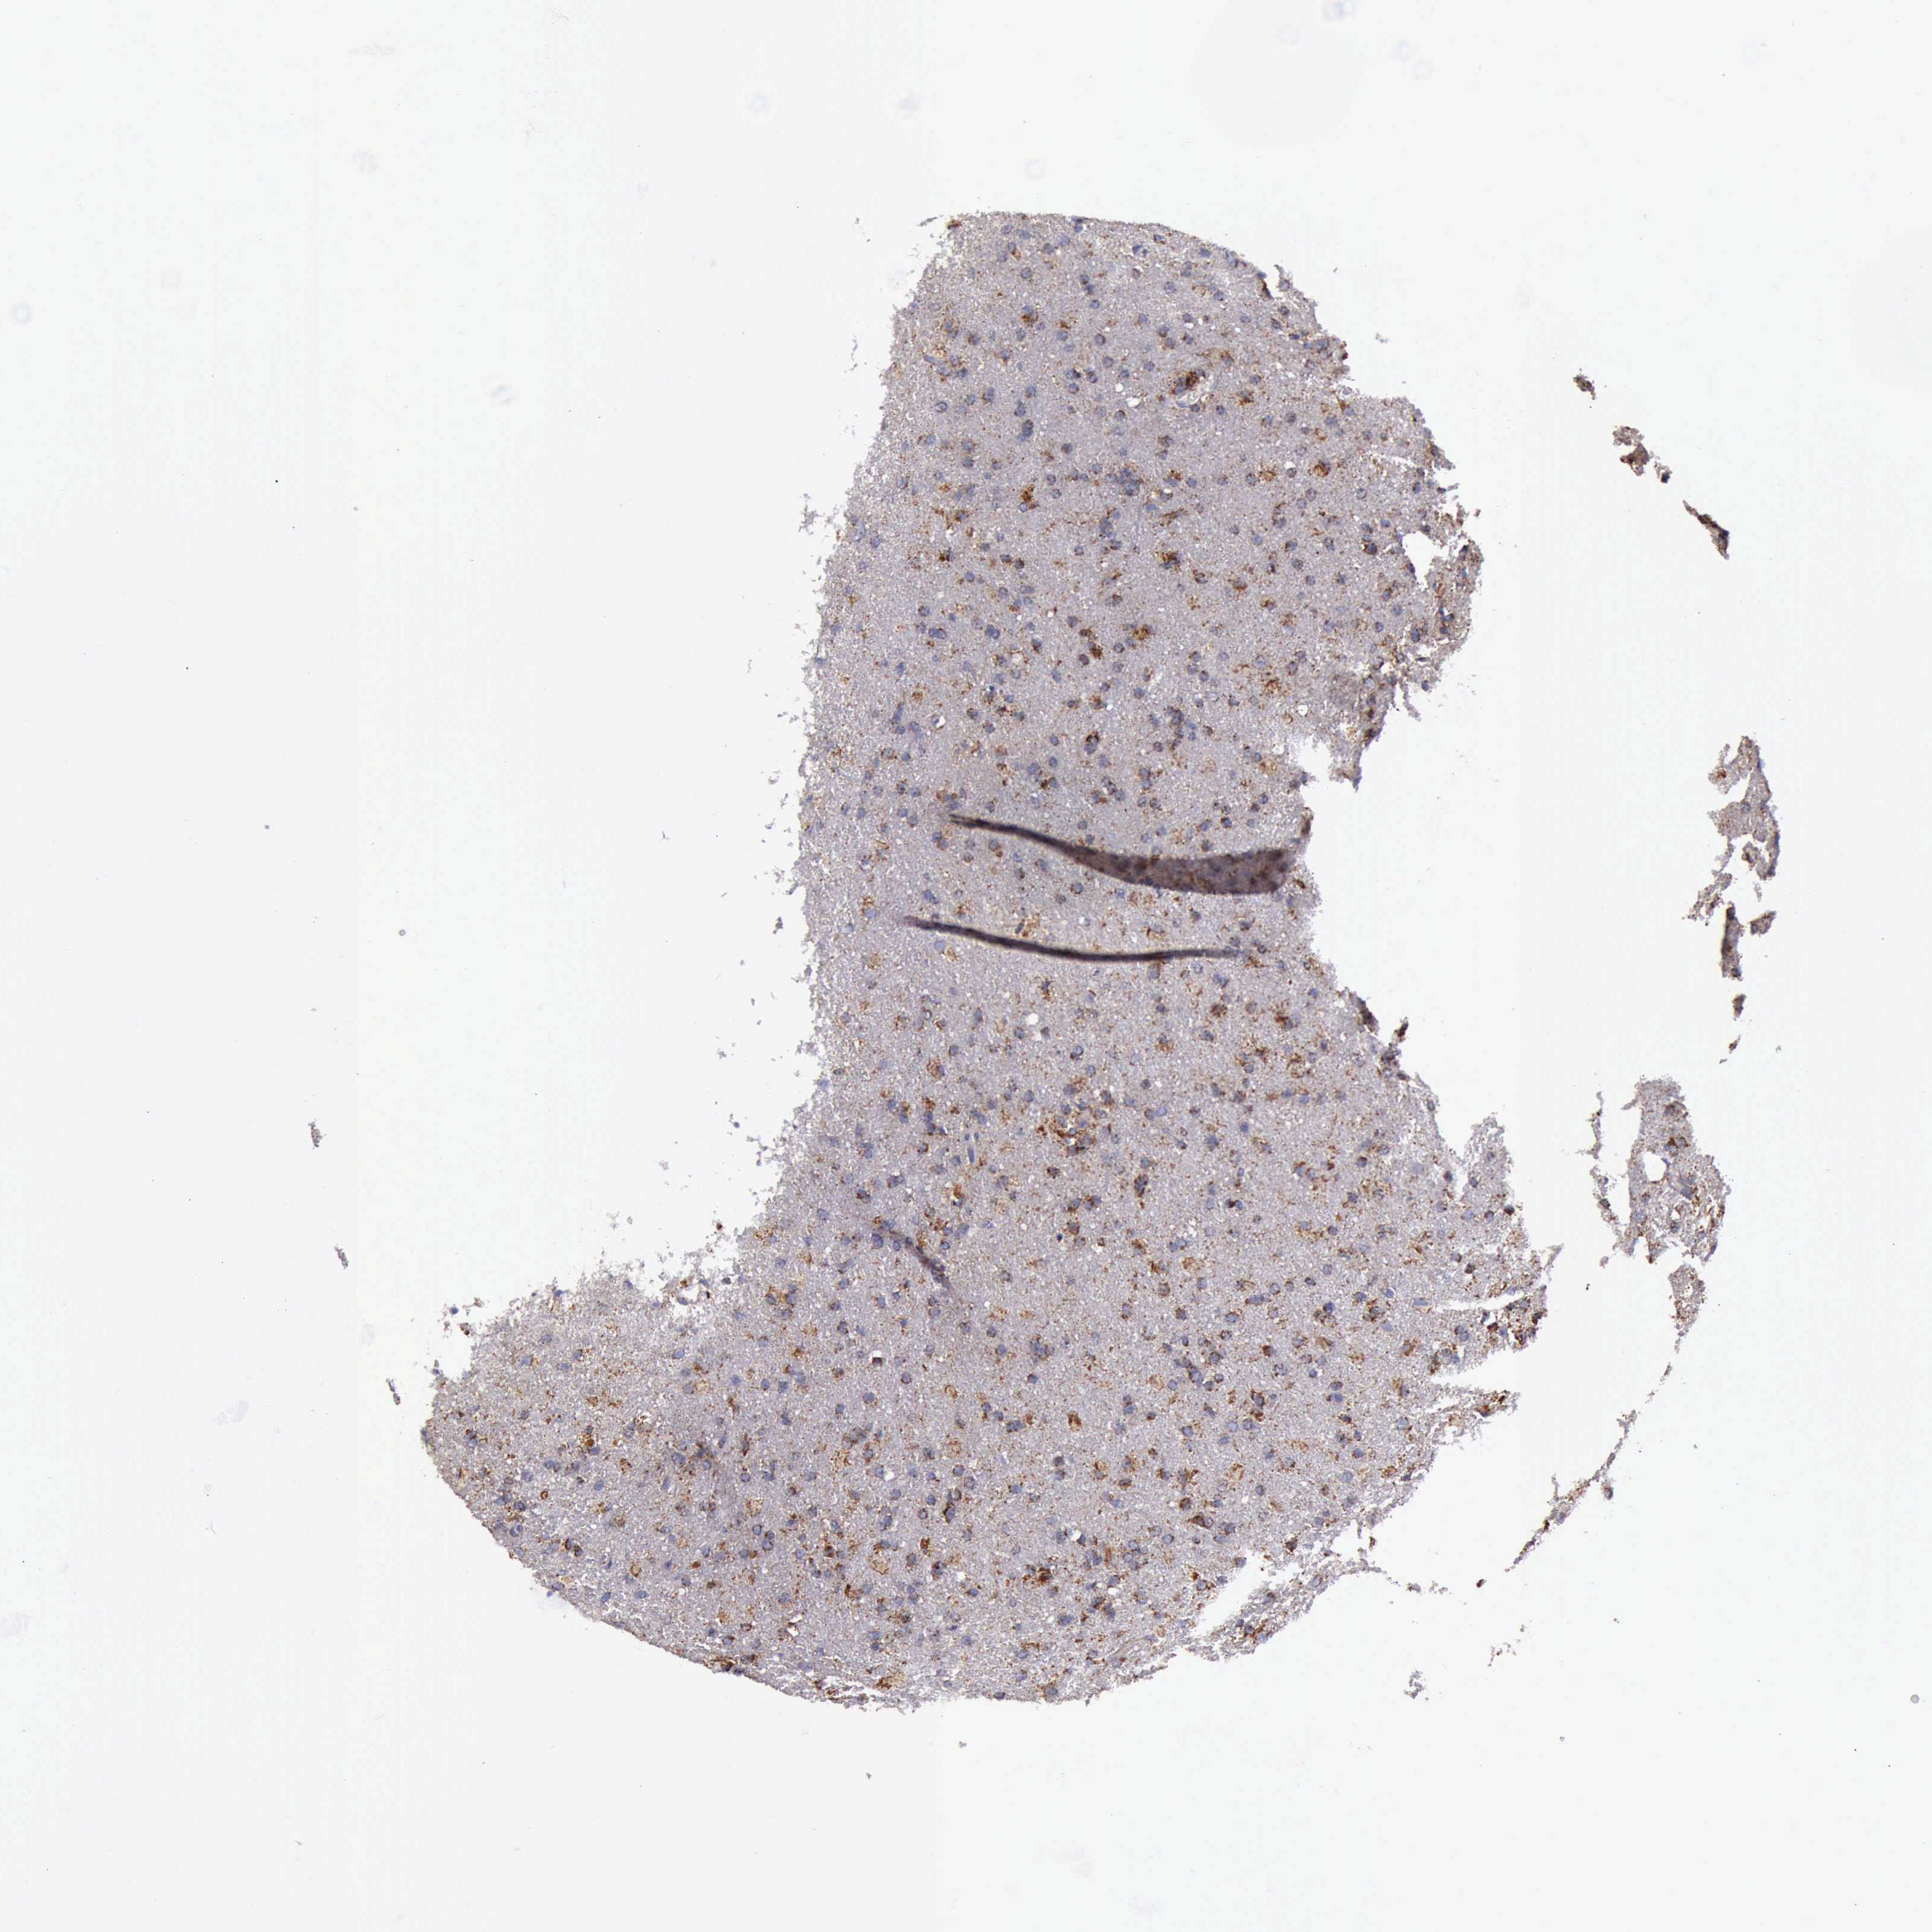

GLIOMA - Protein expressioni

A mouse-over function shows sample information and annotation data. Click on an image to view it in a full screen mode. Samples can be filtered based on level of antibody staining by selecting one or several of the following categories: high, medium, low and not detected. The assay and annotation is described here.

Note that samples used for immunohistochemistry by the Human Protein Atlas do not correspond to samples in the TCGA dataset.

Antibody stainingi

Antibody staining in the annotated cell types in the current human tissue is reported as not detected, low, medium, or high, based on conventional immunohistochemistry profiling in selected tissues. This score is based on the combination of the staining intensity and fraction of stained cells.

Each image is clickable and will lead to virtual microscopy that enables deeper exploration of all samples and also displays staining intensity scores, fraction scores and subcellular localization as well as patient and tissue information for each sample.

Antibody HPA000994

Antibody CAB008681

Staining

High

Medium

Low

Not detected

Intensity

Strong

Moderate

Weak

Negative

Quantity

>75%

75%-25%

<25%

None

Location

Nuclear

Cytoplasmic/membranous

Cytoplasmic/membranous,nuclear

Glioma, malignant, High grade

Glioma, malignant, Low grade